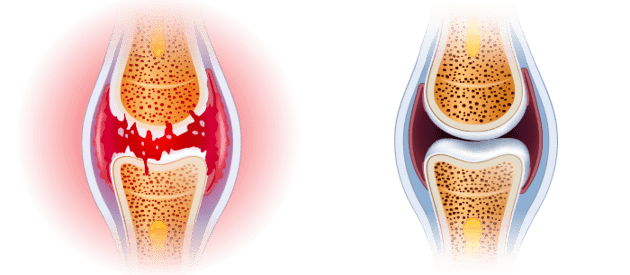

La articulación y la columna se desgastan con el paso de los años, pero si también se rompen por el sobrepeso, el trabajo físico extenuante, el transporte de objetos pesados, el exceso de deporte, las lesiones y los hematomas. El líquido sinovial y el cartílago han sido destruidos. Las juntas suenan como un tamiz sin lubricar: empieza a desgastarse y a degradarse constantemente. Con el tiempo, comienza a sentirse rígido y con un dolor insoportable que le impide moverse con normalidad. Si desarrollan inflamación y degeneración grave.

Desafortunadamente, las células del cartílago y del líquido sinovial no tienen la capacidad de curarse por sí mismas. Esto significa que, a diferencia de otras células del cuerpo humano, no podemos volver a estar sanos. Por eso las articulaciones y la columna empeoran día a día. Eso sí, no cambies la caminata y aprovecha las actividades diarias para proteger tus articulaciones y columna. Sería absurdo.

La fórmula única de Arthrozax actúa desde el interior del cuerpo, desactivando el dolor a nivel celular y permitiéndote seguir con tu vida sin molestias. Gracias a sus propiedades estimula la nutrición celular, lo que restablece los procesos regenerativos en un 300%. Al mismo tiempo, los ingredientes naturales inician los procesos de regeneración automática del cartílago y del líquido sinovial. El uso diario de las crema Arthrozax es suficiente para que el proceso de regeneración ocurra de forma continua las 24 horas del día. Haz lo que haces siempre y tus articulaciones y columna se rejuvenecerán y recuperarán la movilidad. De esta forma, la degeneración y el dolor desaparecen para siempre en 30 días. ¡Sin efectos secundarios!

ANTES

Articulación destruida y afectada por degeneración y dolor

DESPUÉS

Articulación regenerada: 100% sana y sin dolor